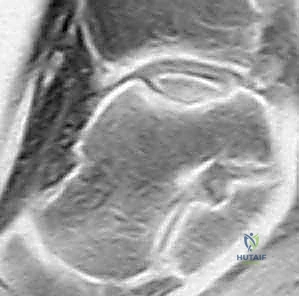

We use the Dipaola et al. MRI classification, based on Berndt and Harty's original radiographic system, to stage the lesion:

* Stage I: Thickening of articular cartilage and low signal changes.

* Stage II: Articular cartilage breached, low-signal rim behind the fragment indicating fibrous attachment.

* Stage III: Articular cartilage breached, high-signal changes behind the fragment indicating synovial fluid between the fragment and underlying subchondral bone. (This is what we see in our current case.)

*

* FIG 3 • Sagittal MRI (T2-SE-2000/90) showing an osteochondral lesion stage III.

* Stage IV: Loose body.